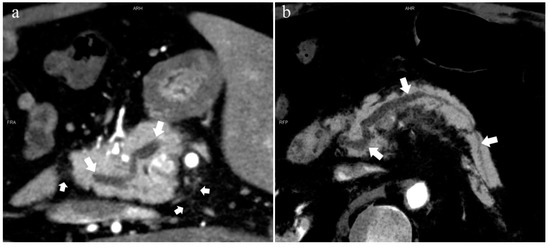

Figure 6.

Type 4b. A 46-year-old male patient with hilar cholangiocarcinoma. (a): MIP [45 keV MEI (+)] shows that the MPD (long arrow) flows into the MiP and extends to the tail. APD is not shown. The initial part of the common bile duct (short arrow) is visible. (b): MinIP [45 keV MEI (+)] shows the course of the pancreatic duct more clearly. MPD refers to anatomically large and functionally dominant ducts.

Figure 7.

Complete pancreas division (Type 4a). A 42-year-old female patient with common bile duct stones. (a): MIP [45 keV MEI (+)] shows that the MPD (long arrow) flows into the MiP (arrowhead) and the APD (short arrow) flows into the MP. There is no communication between MPD and APD. The T-tube (black arrow) can be seen in MP and the common bile duct. (b): MinIP [45 keV MEI (+)] more intuitively shows the overall shape of MPD (long arrow) and APD (short arrow). MPD flows into MiP and extends to the tail of the pancreas. (c): Oblique coronal thick slab MRCP image shows MPD (long arrow) flows into the MiP (short arrow) and the APD is not displayed. The stone (arrowhead) is located in the middle and lower part of the common bile duct. MPD refers to anatomically large and functionally dominant ducts.

Figure 8.

Type 4c. A 73-year-old female patient with multiple stones of the intrahepatic bile duct. (a): MIP [45 keV MEI (+)] shows that MPD (long arrow) flows into MiP, and APD (short arrow) flows into MP with a small communication branch (bent arrows) between them. (b): MinIP [45 keV MEI (+)] improves visualization of small pancreatic ducts and their branches. MPD refers to anatomically large and functionally dominant ducts.